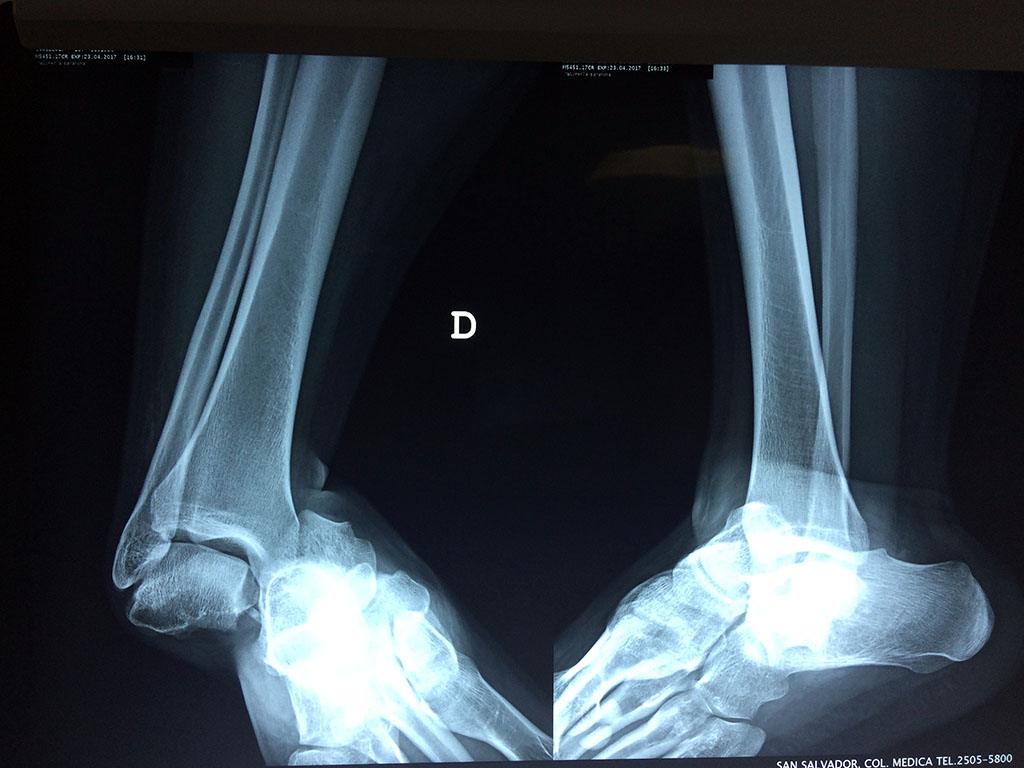

Una fractura de tobillo es la rotura de uno o más de los huesos del tobillo. Estas fracturas pueden ser:

- Los extremos de los huesos están desalineados entre sí (desplazados).

- La fractura se extiende hasta la articulación del tobillo (fractura intra-articular).